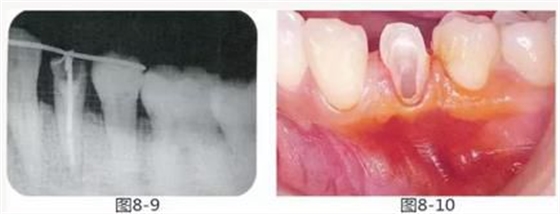

圖8-9 同時(shí)期的X光照片。牙槽骨無(wú)變化。

圖8-10 約一個(gè)月后,進(jìn)行牙周外科治療之前的狀態(tài)。附著齦較少。